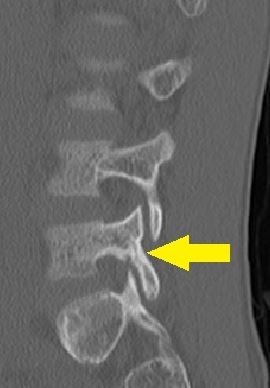

- CT画像

L5左は腰椎分離症終末期